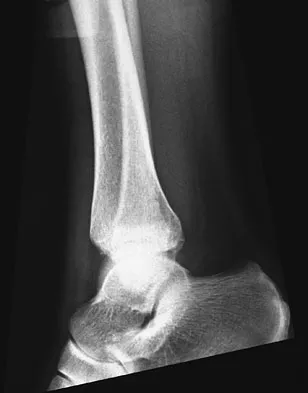

Figures 4a through 4c show the radiographs of a 43-year-old woman who sustained a twisting injury to her right ankle. She has ankle pain and tenderness medially and laterally. To help determine the optimal treatment, an external rotation stress radiograph of the ankle is obtained. This test is designed to evaluate the integrity of what structure?

Explanation

In the presence of a supination external rotation-type fracture of the distal fibula (Weber type B), stability of the ankle is best assessed by performing an external rotation stress AP view of the ankle. This test is used to assess the integrity of the deltoid ligament. The presence of a deltoid ligament rupture results in instability and generally is best managed surgically. The gravity stress test can also be used. Egol KA, Amirtharajah M, Tejwani NC, et al: Ankle stress test for predicting the need for surgical fixation of isolated fibular fractures. J Bone Joint Surg Am 2004;86:2393-2398. McConnell T, Creevy W, Tornetta P III: Stress examination of supination external rotation-type fibular fractures. J Bone Joint Surg Am 2004;86:2171-2178.